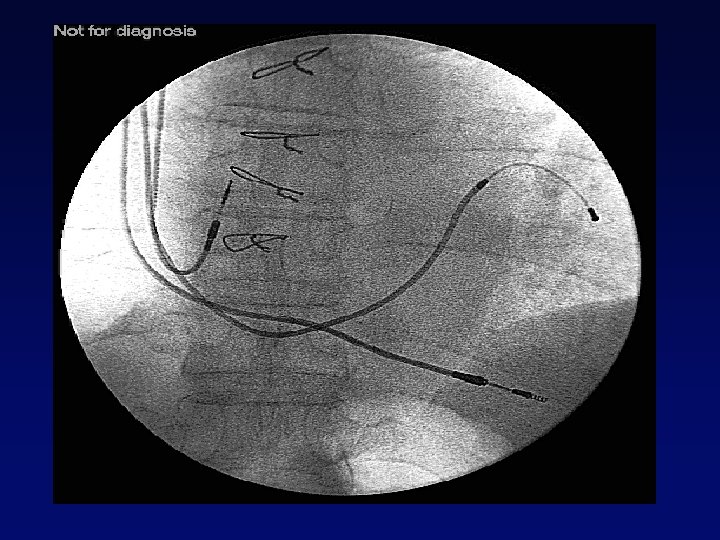

Venografia retrograda del seno coronarico Perforazione di piccola vena e impianto in v. poster-laterale OAS C D’Ascia, G Riccio Università degli Studi di Napoli Federico II

Posizionamento Elettrocatetere Elettrocateteri Introduzione Elettrocatetere Rimozione Catetere Guida Introduzione Guida Venografia Retrograda OSC Introduzione Catetere Guida Easytrak e Rimozione Atriale e Ventricolare Dx Easytrak su Guida BMW e Guida Finishing Wire Giuda BMW C D’Ascia, G Riccio Università degli Studi di Napoli Federico II

Venografia retrograda del seno coronarico v. ant Elettrodo in v. ant v. cm v. lat OAS C D’Ascia, G Riccio Università degli Studi di Napoli Federico II Posizionamento in Vena Interventricolare Anteriore

Vengrafia retrograda del seno coronarico Elettrodo in v. lat OAS C D’Ascia, G Riccio Università degli Studi di Napoli Federico II Posizionamento in Vena Laterale